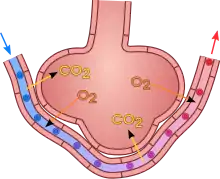

A pulmonary alveolus (pl.: alveoli, from Latin alveolus, "little cavity"), also known as an air sac or air space, is one of millions of hollow, distensible cup-shaped cavities in the lungs where pulmonary gas exchange takes place.[1] Oxygen is exchanged for carbon dioxide at the blood–air barrier between the alveolar air and the pulmonary capillary.[2] Alveoli make up the functional tissue of the mammalian lungs known as the lung parenchyma, which takes up 90 percent of the total lung volume.[3][4]

Alveoli are first located in the respiratory bronchioles that mark the beginning of the respiratory zone. They are located sparsely in these bronchioles, line the walls of the alveolar ducts, and are more numerous in the blind-ended alveolar sacs.[5] The acini are the basic units of respiration, with gas exchange taking place in all the alveoli present.[6] The alveolar membrane is the gas exchange surface, surrounded by a network of capillaries. Oxygen is diffused across the membrane into the capillaries and carbon dioxide is released from the capillaries into the alveoli to be breathed out.[7][8]

An alveolus consists of an epithelial layer of simple squamous epithelium (very thin, flattened cells),[13] and an extracellular matrix surrounded by capillaries. The epithelial lining is part of the alveolar membrane, also known as the respiratory membrane, that allows the exchange of gases. The membrane has several layers – a layer of alveolar lining fluid that contains surfactant, the epithelial layer and its basement membrane; a thin interstitial space between the epithelial lining and the capillary membrane; a capillary basement membrane that often fuses with the alveolar basement membrane, and the capillary endothelial membrane. The whole membrane however is only between 0.2 μm at its thinnest part and 0.6 μm at its thickest.[14]

In the alveolar walls there are interconnecting air passages between the alveoli known as the pores of Kohn. The alveolar septum that separates the alveoli in the alveolar sac contains some collagen fibers and elastic fibers. The septa also house the enmeshed capillary network that surrounds each alveolus.[3] The elastic fibres allow the alveoli to stretch when they fill with air during inhalation. They then spring back during exhalation in order to expel the carbon dioxide-rich air.